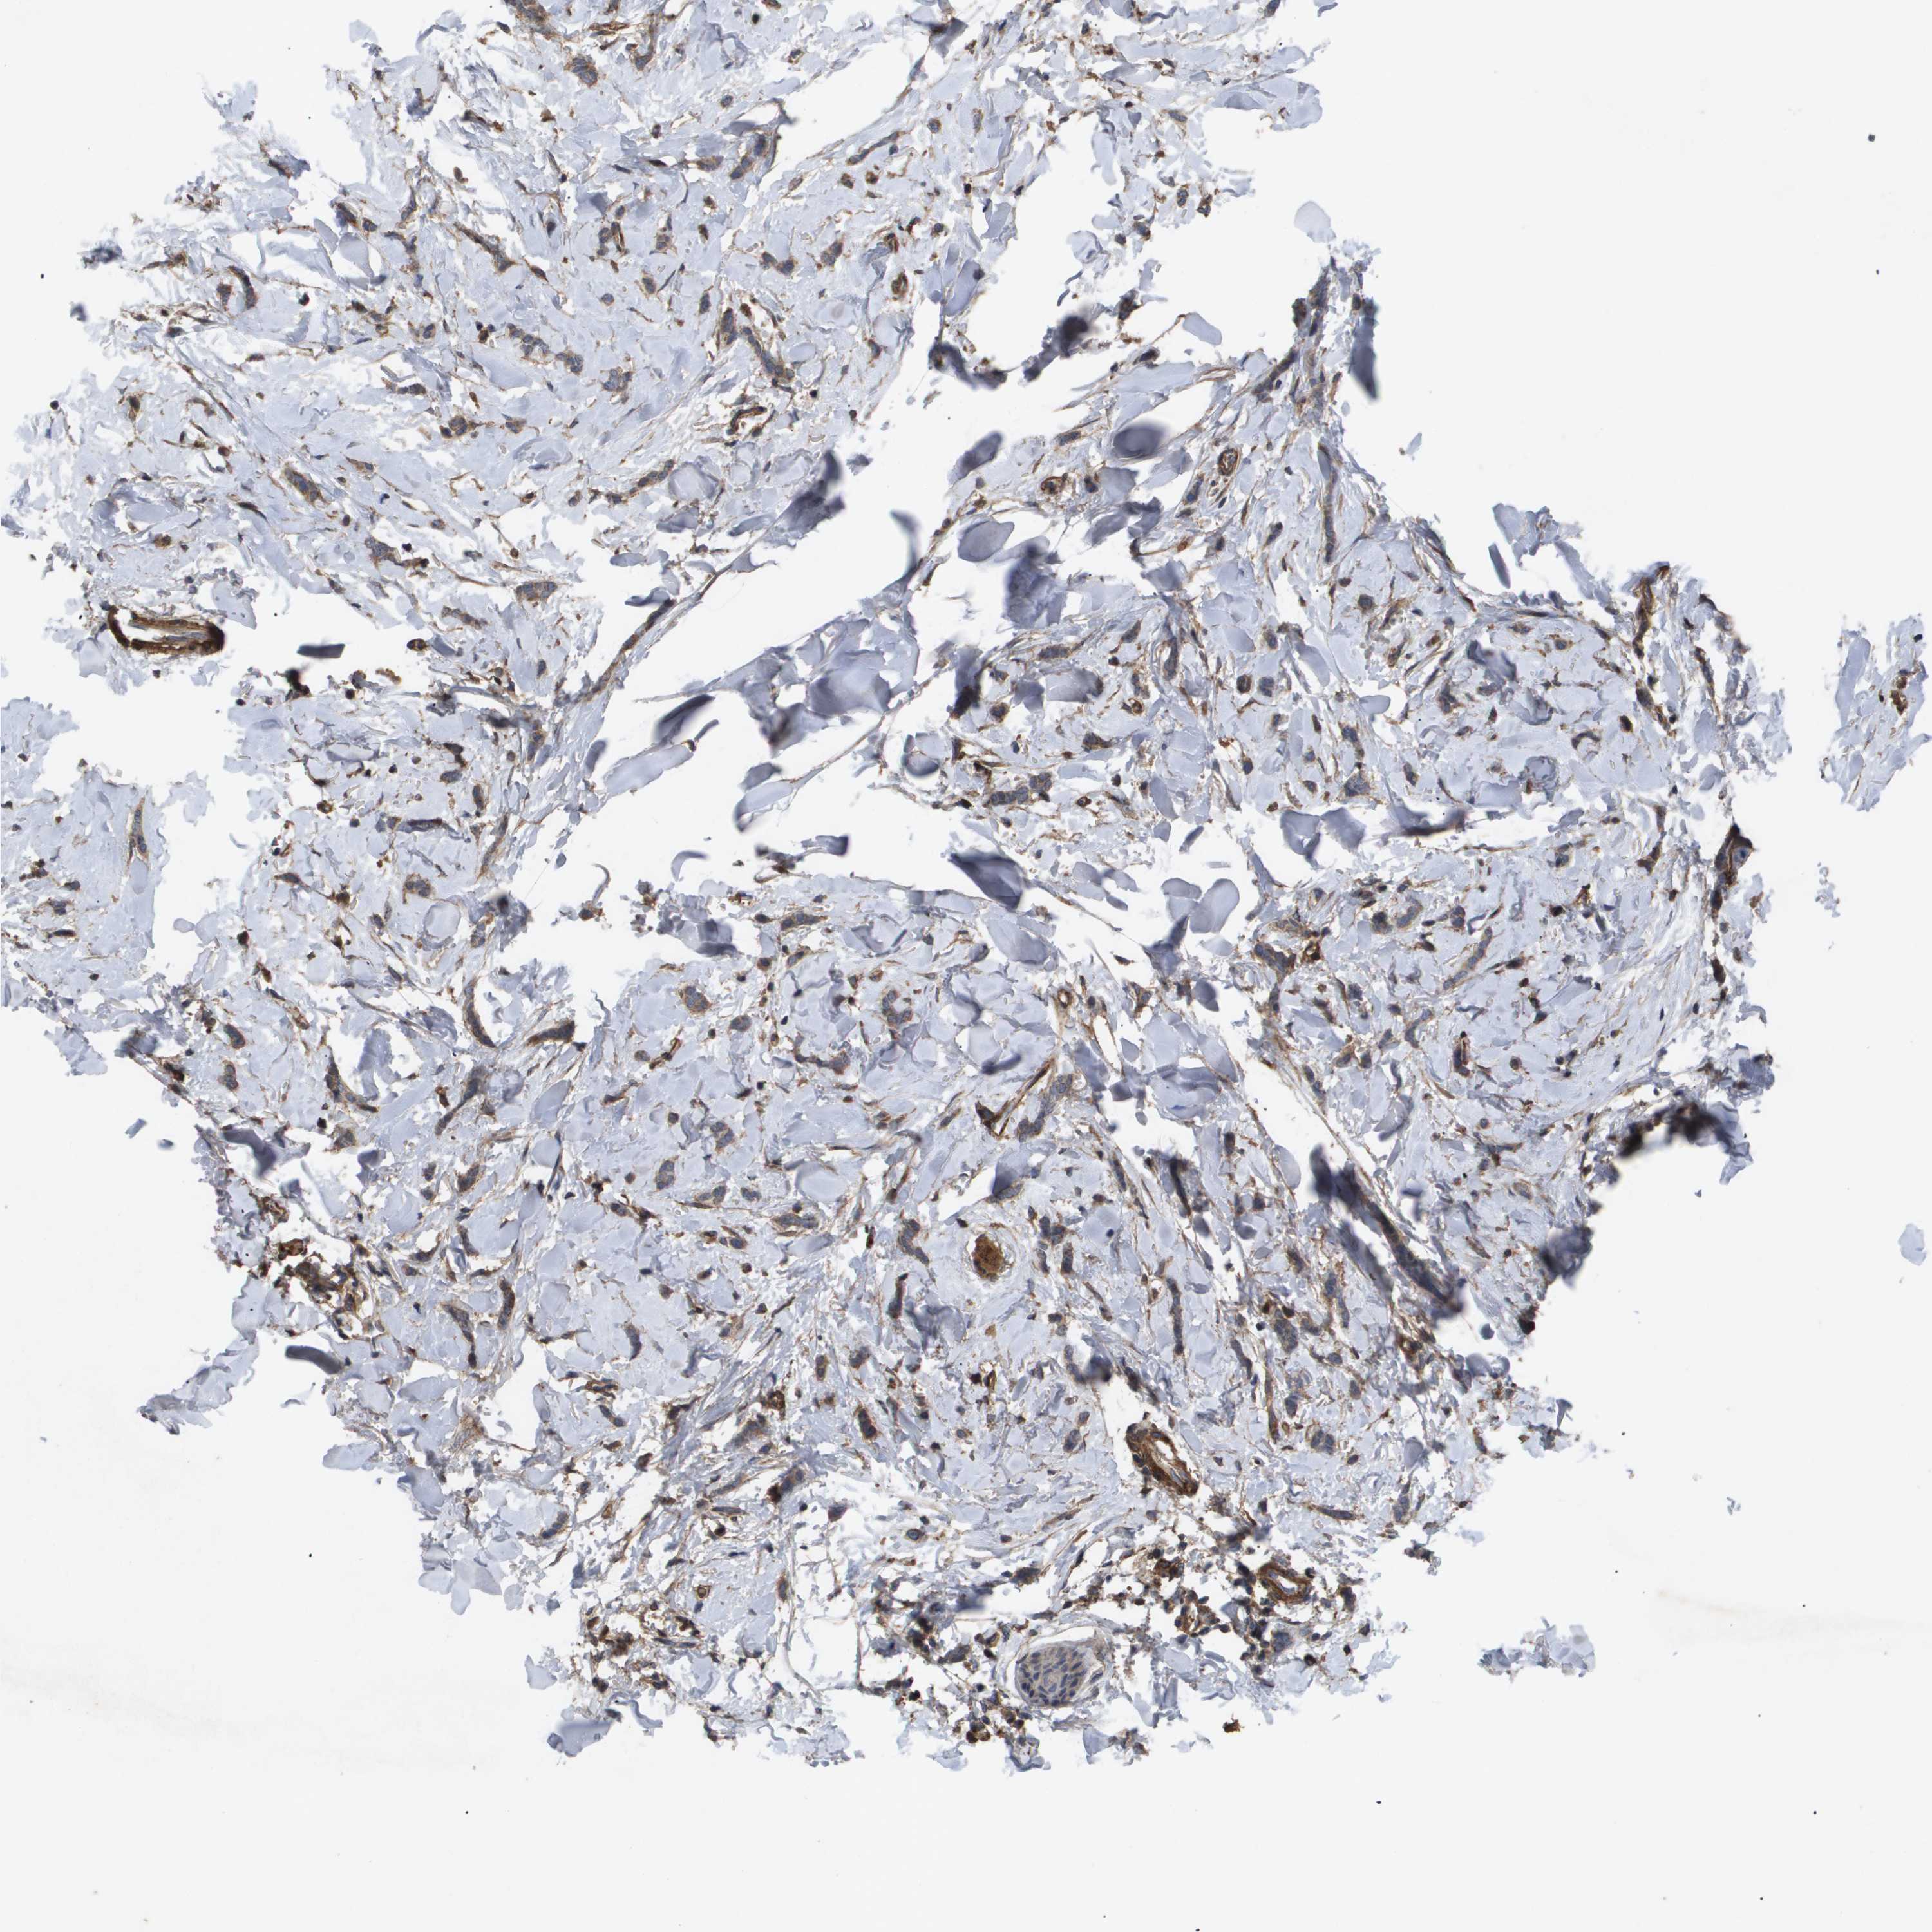

CANCER BREAST CANCER Show tissue menu

BRCA TCGA BRCA VALIDATION PROTEIN EXPRESSION